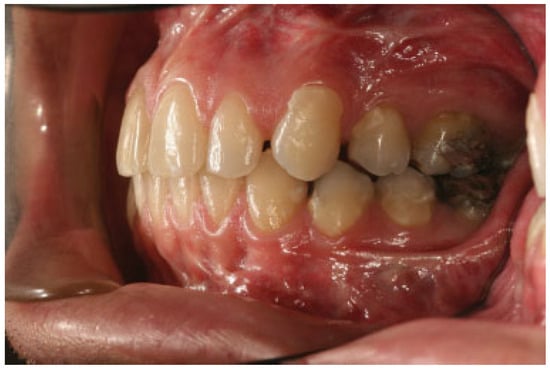

:Case Report